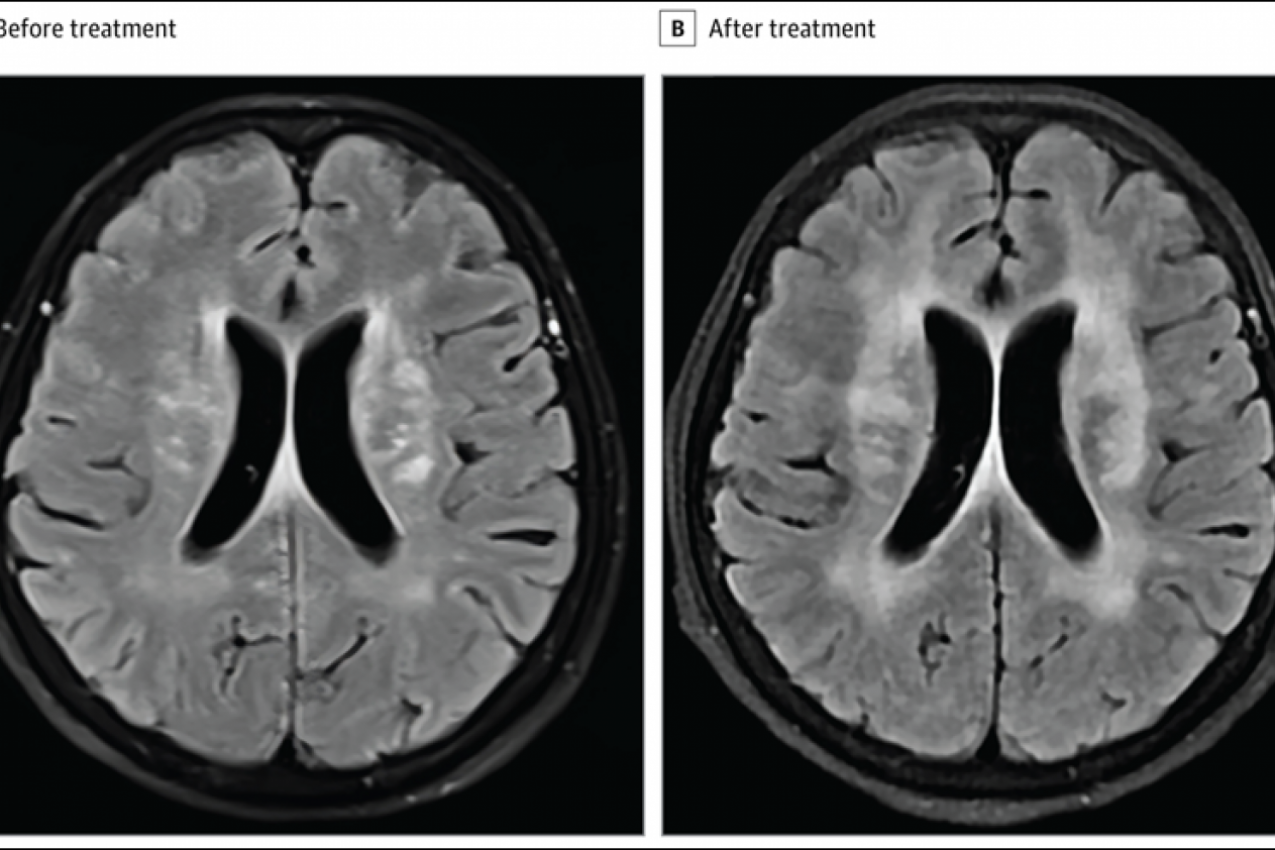

Kada su uzeli u obzir njene simptome, doktori su smatrali da je meningitis najlogičniji uzrok. To je potvrdio i nalaz magnetne rezonance koji je pokazao da žena na mozgu ima brojne lezije, koje mogu da budu znak infekcije, ali i dokaz da se radi o meningitisu.

Ali, posle dve nedelje antibiotika, ona se osećala sve gore. a lezije na mozgu su se samo uvećale.

Posle četiri meseca, snimak njenog mozga je pokazao da su se lezije drastično smanjile, i ona se skoro u potpunosti oporavila, prenosi San (The Sun).